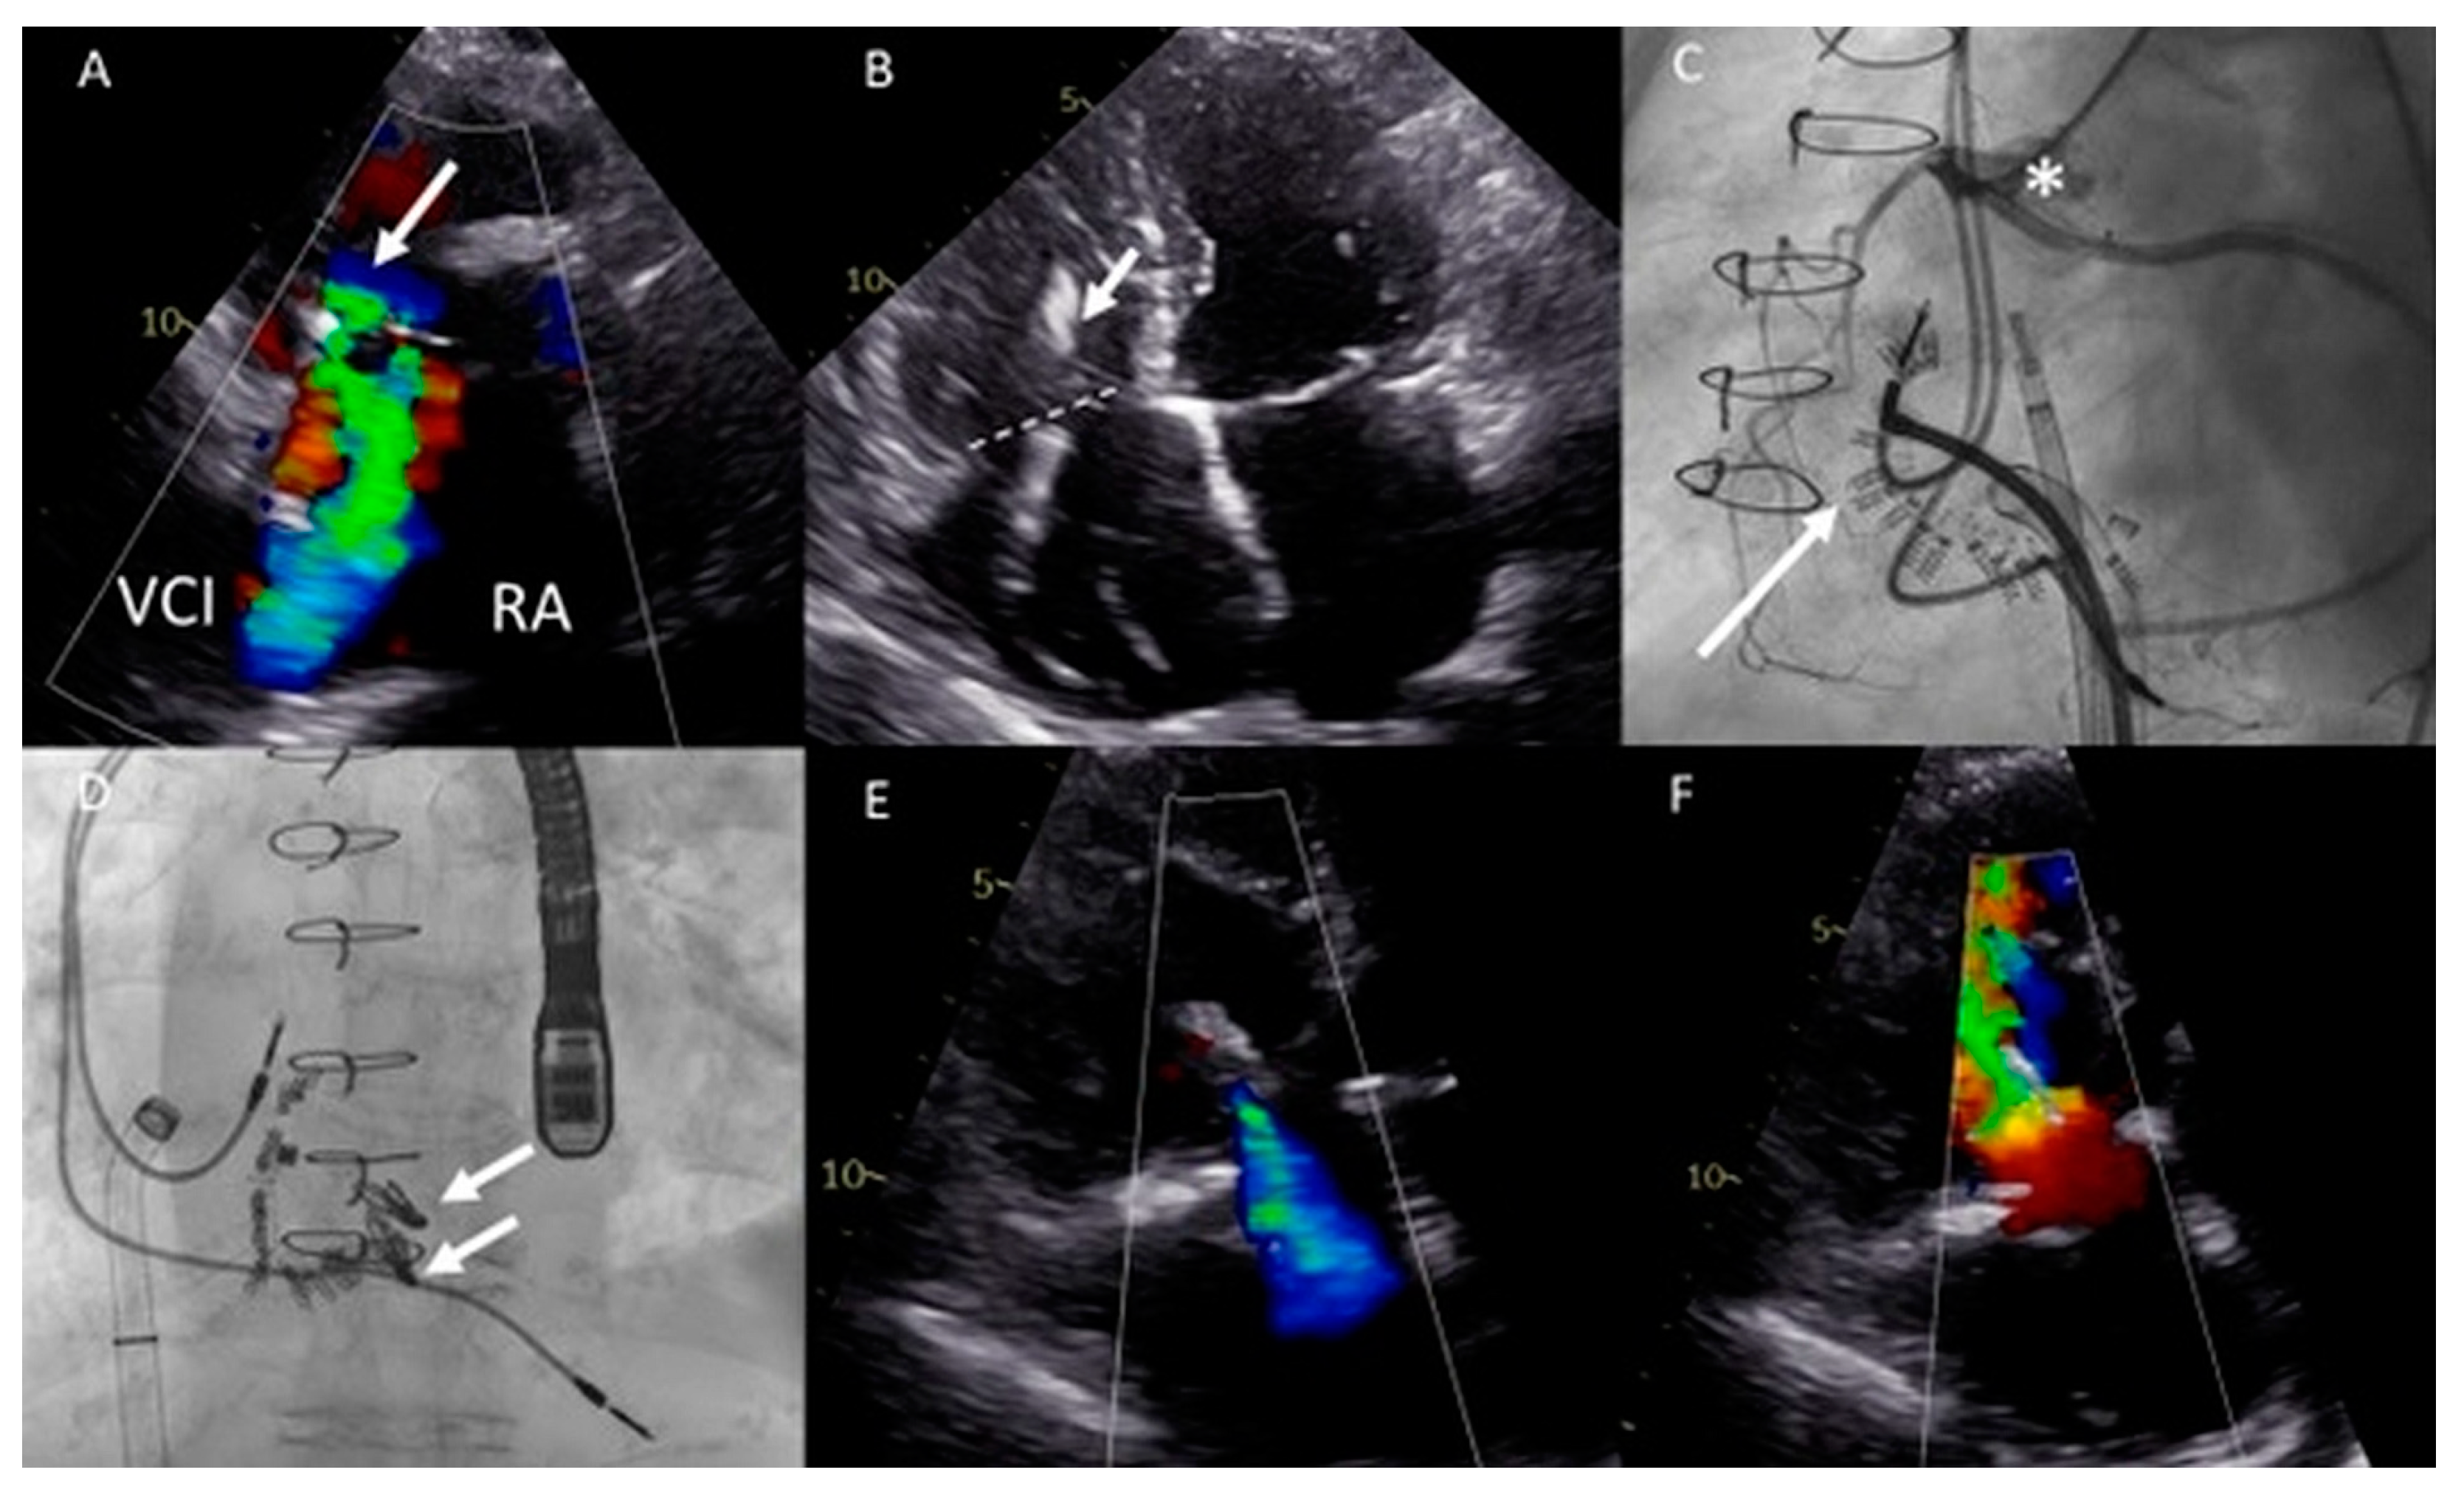

Figure 6.

(A,B) Computed tomography (CT) scan of the thoracic cavity with the anatomical position of the dilated functional mono-atrium (asterisk) against the right thoracic wall (panel A) and bidirectional bilateral Glenn shunt (panel B) (LPA = left pulmonary artery, RPA = right pulmonary artery, LSVC = left superior vena cava, RSVC = right superior vena cava). (C) Pre-procedural transesophageal echocardiography (TEE) which visualized severe common atrioventricular (AV) valve regurgitation. (D) Anteroposterior fluoroscopic view of the two XTW MitraClips positioned in the AV valve. At the same time, it is appreciated that the delivery system is positioned through the fifth intercostal space after a right mini-lateral thoracotomy. (E) Moderate AV regurgitation after the hybrid procedure visualized with TEE.

Conventional surgical AV valve replacement or repair was considered extremely high risk due to the anatomical relation between the atrium and the thoracic wall, the extensive coronary fistulae, and the reduced ventricular function. Percutaneous AV valve replacement or repair was deemed non-feasible by the transvenous route due to interruption of the IVC with azygos continuation and sharp angulation into the mono-atrium (for a transfemoral approach). Furthermore, a transjugular approach was not feasible because of the bilateral Glenn connection. Therefore, it was decided that a hybrid procedure under general anesthesia with direct atrial access using a MitraClip delivery system (Abbott, IL, USA) was the best strategy.

The congenital cardiothoracic surgeon performed a right (mini) lateral thoracotomy in the fifth intercostal space to expose the giant mono-atrium. A double-purse string suture was placed and an incision was made to create an opening using a Safari wire for guidance and stability. The interventional cardiologist then placed two XTW clips under TEE guidance (Figure 6D), resulting in reduction in AV valve regurgitation to grade II (Figure 6E). Post-procedural TEE showed grade II regurgitation with stable position of the clips. No peri-procedural complications occurred. The patient could be discharged with adequate heart failure medication with an improvement in NYHA functional class (II). Unfortunately, the patient died after 9 months due to progressive ventricular dysfunction, worsening of the AV valve regurgitation, and heart-failure-related multi-organ dysfunction (NYHA functional class IV at the latest admission).

Figure 7.

(A) Color Doppler modified parasternal right ventricular (RV) inflow view shows severe tricuspid regurgitation (TR) with a wide vena contracta (arrow) and leakage jet reaching the inferior vena cave (IVC). (B) Apical four-chamber view shows tricuspid valve (TV) annulus dilatation (dash line, 46 mm) and impingement by the RV pacemaker lead (arrow). (C) Left inferior oblique fluoroscopic view of the Cardioband (arrow) annulus reduction procedure (asterisk). (D) Anteroposterior fluoroscopic view shows the two XTW clips (arrows) implanted. (E,F) Modified apical four chamber color Doppler views showing mild (-moderate) residual TR and inflow through the TV (mean gradient of 3 mmHg).

Both procedures were performed in sequential order under general anesthesia, by means of right femoral access and fluoroscopy and transesophageal echocardiographic guidance (Figure 7C,D). A total of 15 anchors were used for the Cardioband annular reduction (Edwards Lifesciences, USA) reducing the annulus dimensions to 28 × 27 mm. Yet, moderate-severe TR persisted and the second procedure was planned for the patient. She underwent the placement of two TriClips (Abbott, IL, USA), resulting in reduction of TR to mild-moderate and a slightly elevated inflow gradient of 3 mmHg over de TV (Figure 7E,F). No periprocedural complications were documented. At 16 months follow-up, the patient remains in NYHA functional class II and is euvolemic. No heart-failure-related admissions occurred since the TV interventions.